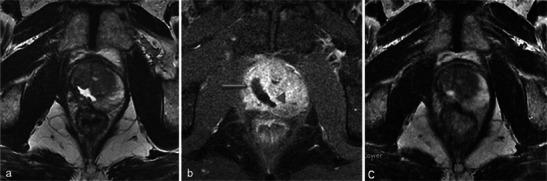

In this technique, a photosensitising agent is introduced intravenously, then activated by local laser illumination to induce tumour necrosis. Treatment efficacy is assessed by magnetic resonance imaging (MRI).

We illustrate specific post-treatment MRI aspects at early and late follow-up with pathological correlations.

• Dynamic phototherapy is a new and promising focal therapy for prostate cancer. • One-week MRI shows increased volume of the treated lobe and large, homogeneous necrosis area. • Six-month MRI shows significant changes of the prostate shape and signal. • Six-month MRI becomes "base line" appearance for further follow-up or monitoring.

在该技术中,将一种光敏剂静脉注射,然后通过局部激光照射激活以诱导肿瘤坏死。通过磁共振成像(MRI)评估治疗效果。

我们阐述了早期和晚期随访时特定的治疗后MRI表现及其与病理的相关性。

• 动态光动力疗法是一种用于前列腺癌的新型且有前景的局部治疗方法。• 一周后的MRI显示治疗叶体积增大以及大片均匀的坏死区域。• 六个月后的MRI显示前列腺形态和信号有显著变化。• 六个月后的MRI成为进一步随访或监测的“基线”表现。